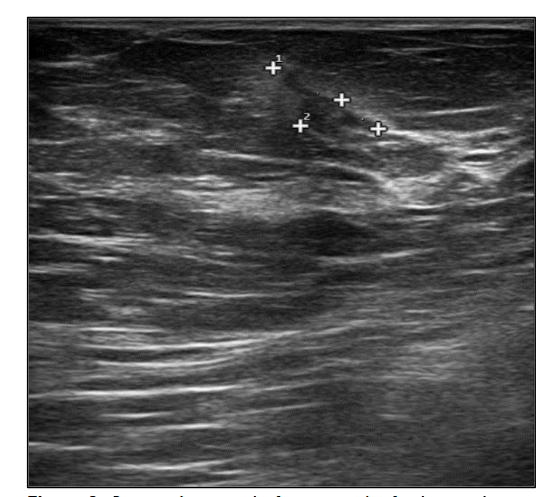

We stopped azacitidine and we promptly biopsied the nodule with a diagnosis of breast infiltration by AML blasts carrying the NPM1 mutation. CT scan and PET of chest, neck and abdomen were negative, and BM evaluation showed 1% blasts, with NPM1 0.044. The FLT3-ITD mutation resulted positive on breast cells while negative on medullary blasts. Thus, concluding for extramedullary relapse of AML FLT3-ITD mutated, we decided to start gilteritinib as single agent, at a dose of 120 mg daily. After 30 days, mammary ultrasound showed a reduction in diameter of the nodule.

In 4 months, the lesion has completely disappeared. The PET scan performed after 5 months of treatment was persistently negative and confirmed the absence of other uptakes. BM re-evaluation showed no blasts, with NPM1 0.006. Today, after 44 months of treatment, our patient is still in CR without signs of clinical and radiologic relapse.